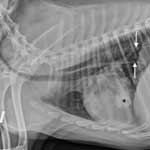

Диагностика пневмонии начинается из рентгена. Это позволяет увидеть, какая часть легких поражена, и критичность ситуации. Также необходимо сдать общий анализ крови. Это позволяет увидеть причину заболевание, возможное наличие аскарид и личинок в организме животного и непосредственно в самих легких. Так как причин появления пневмонии множество, важно обращаться за помощью к опытному специалисту, который будет учитывать не только результаты анализа крови, симптоматику, но также обратит внимание на возраст животного и наличие породных особенностей.

Диагноз. Диагноз на пневмонию ветеринарный специалист клиники ставит комплексно на основании симптомов болезни, проведения лабораторного исследования крови и мочи. Общий анализ крови дает нейтрофильный лейкоцитоз с сдвигом влево, количество эритроцитов и гемоглобина уменьшается. В обязательном порядке больной собаке делается рентгенография и рентгеноскопия легких, на рентгенограмме видны участки затемнения. Рентгенологическое обследование грудной клетки должно проводиться в двух проекциях. Для исключения пневмоний паразитарного происхождения проводят исследование кала на гельминты.

После прослушивания и перкуссии (простукивания) области легких, доктор назначает рентген грудной клетки. Это наиболее информативный метод диагностирования пневмонии. Затемнение и усиленный легочный рисунок на снимке, позволит определить наличие процесса в легких, его вид и величину поражения органа.